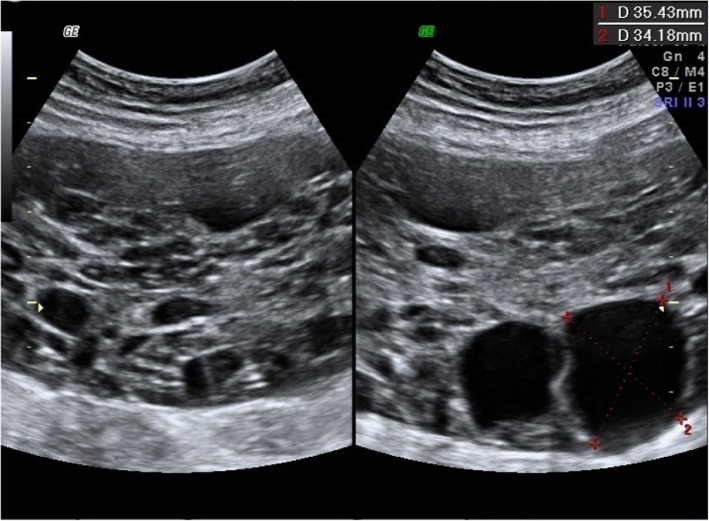

A pelvic ultrasound (U/S), performed in the first trimester of the 4th pregnancy to exclude ovarian causes of hyperandrogenism (luteoma, luteinic cyst or malignant causes), described the single left ovary with an area of 9,9 cm2 and multiple microfollicles. At the same time, a Pelvic Magnetic Resonance Imaging (MRI) confirmed the polycystic ovarian pattern. In the immediate postpartum, another U/S described the polycystic aspect of the left ovary, that was a larger and an anechogenic cyst of 3.5 cm diameter (Fig. 1).

Fig. 1.

U/S of the left ovary in the immediate postpartum (Case 1)